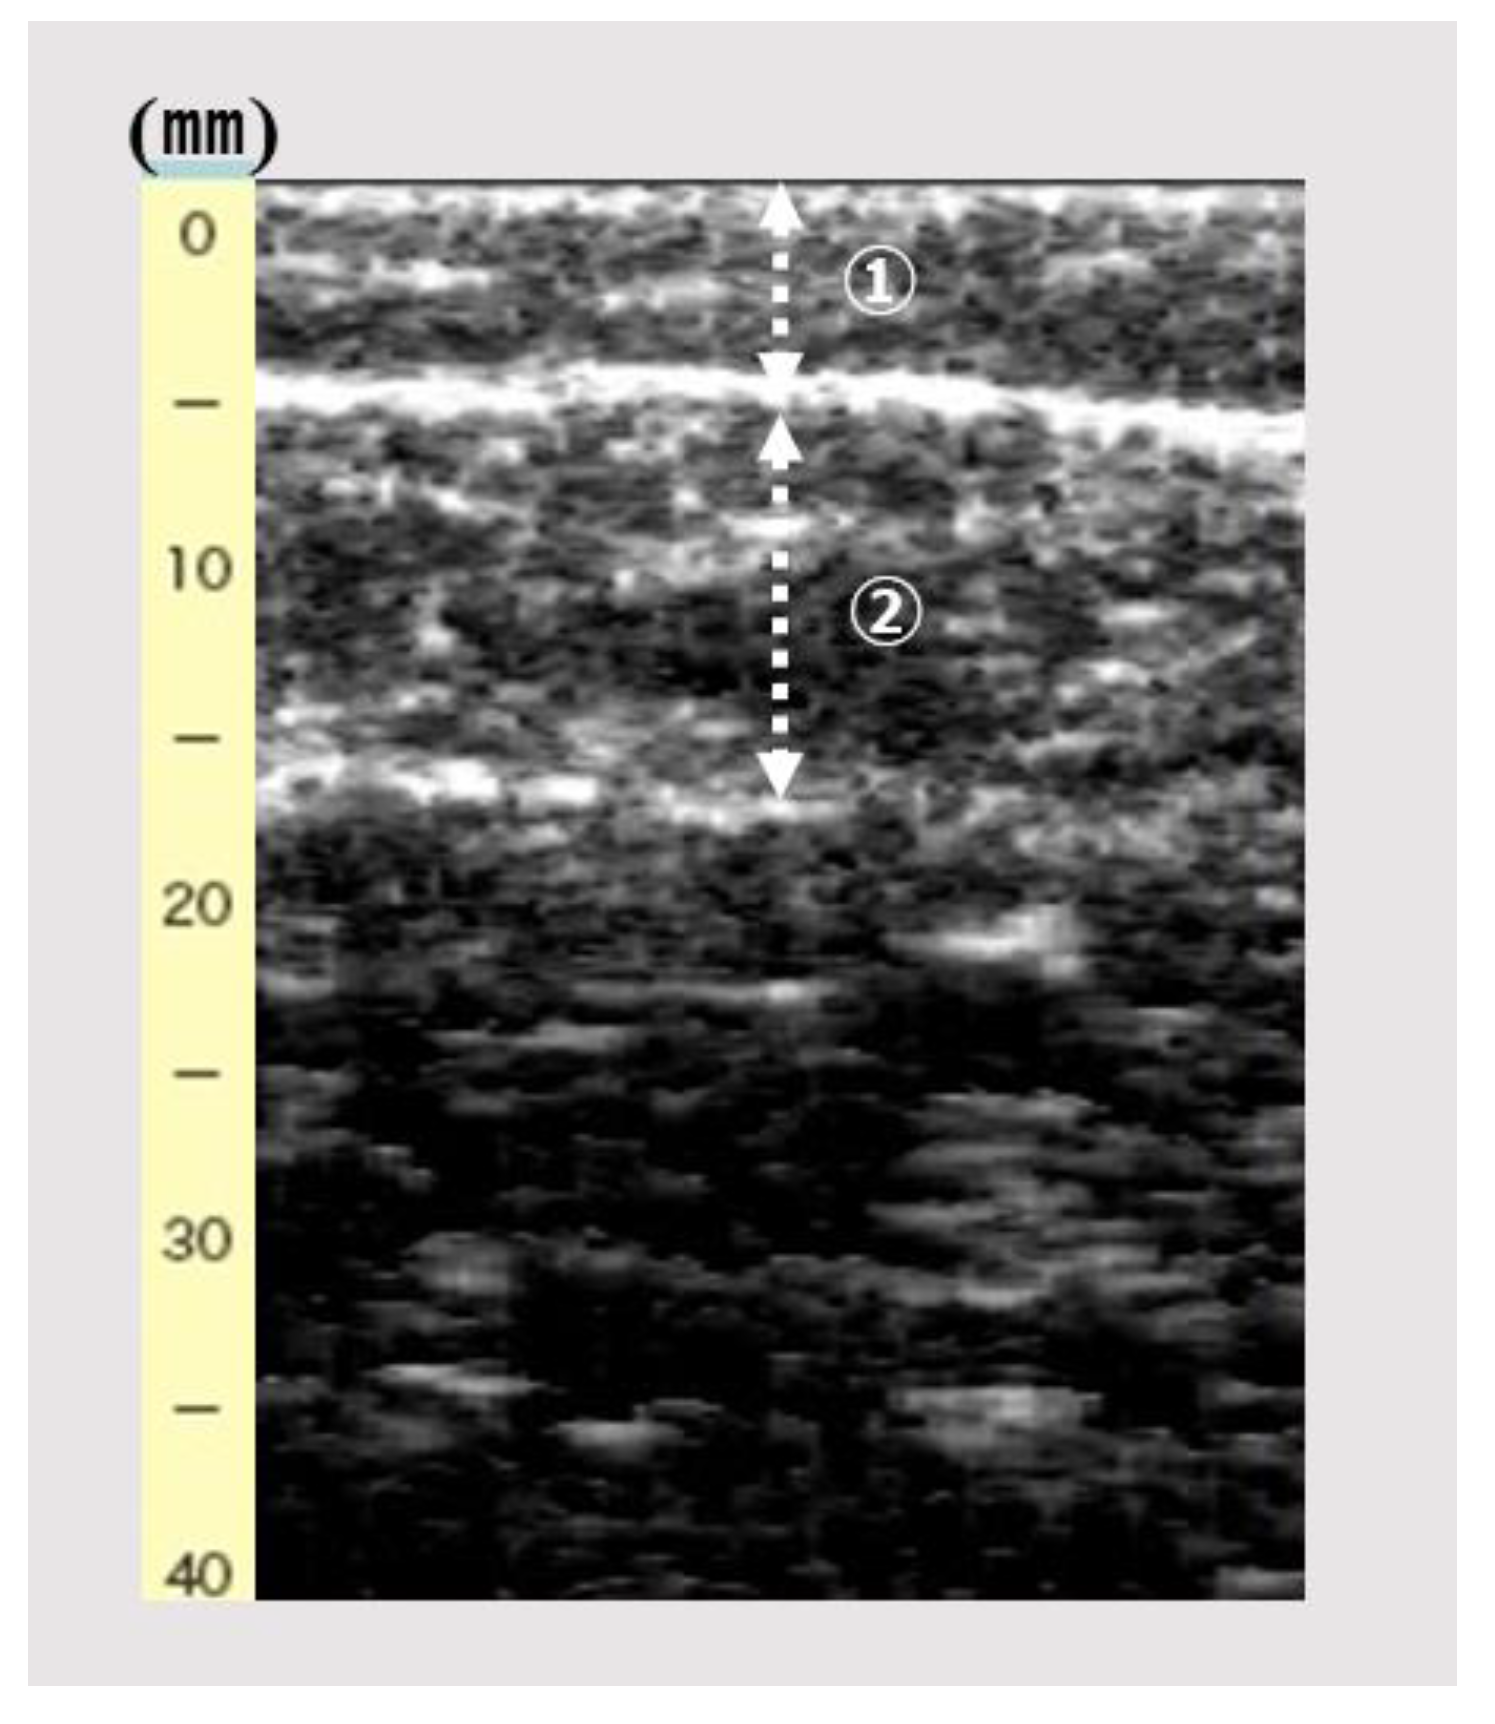

An ultrasound device (View’s i; MINATO Medical Science Co., Ltd., Osaka, Japan) with a 6-MHz linear array probe was used to obtain an image of the gastrocnemius muscle. The ultrasonography setting was consistently set at B-mode and default and fixed dB dynamic range and gain. The participants were assessed while sitting and with the knee joint flexed at 90° and the ankle joint at 0°. While checking the A-mode of the device monitor, the same examiner vertically and lightly placed the probe on the right medial gastrocnemius in the maximum part of the below-knee circumference. The intra-rater reliability was reportedly lower when the pressure was <100 gf [14]. The probe pressure on the skin was controlled at 200 gf. The examiner scanned the image of the subcutaneous adipose tissue and gastrocnemius muscle (Figure 1). Subcutaneous fat thickness (mm) was defined as the distance between the surface and upper fascia of the gastrocnemius; gastrocnemius thickness (mm) was defined as the distance between the subcutaneous to the deep fascia. Subsequently, subcutaneous fat and gastrocnemius thicknesses were measured.

Figure 1.

The image of subcutaneous fat and gastrocnemius thickness by ultrasonography. ➀, Subcutaneous fat thickness (mm); ②, gastrocnemius thickness (mm).

Figure 1 shows the image of subcutaneous fat and gastrocnemius thickness by ultrasonography.